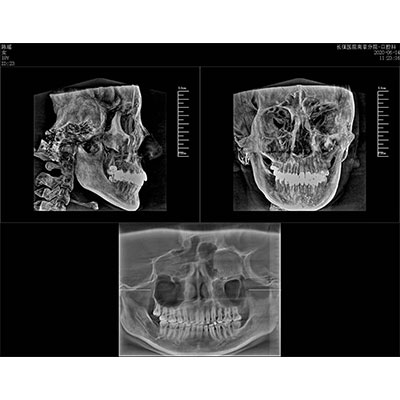

該款牙科CBCT產(chǎn)品采用動(dòng)態(tài)平板探測器,獲得三維圖像的同時(shí)還具有數(shù)字化全景功能,廣泛應(yīng)用于口腔頜面外科、正畸科、正頜外科、種植科、牙體科、顳下頜關(guān)節(jié)科等術(shù)前術(shù)后。

可同時(shí)觀察軸向面、冠狀面和矢狀面圖像,方便臨床診斷。